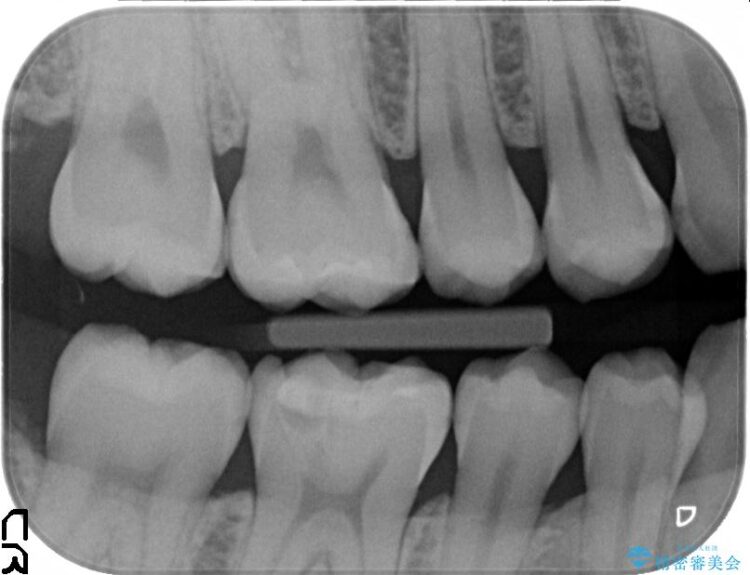

診査をした結果、顎左右の前から6番目の歯に深い虫歯があったため、詰め物(インレー)タイプで修復していく(e-max プレスインレー)での治療を行いました。

今回は歯の黒ずみを気にしてご来院されましたが、診査をしますと神経の治療が必要になる一歩手前の状態である神経の近くまで虫歯が広がっていました。